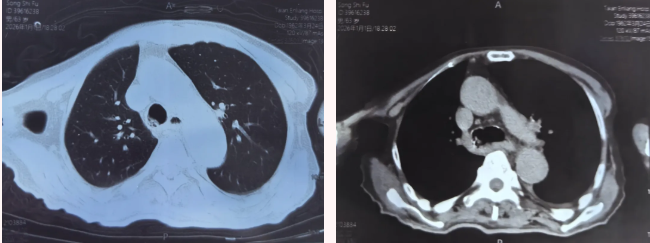

患者生命体征持续恶化,时间异常紧迫。呼吸介入团队到位后迅速评估,决定立即行支气管镜下气道异物取出术。这是对技术和心理的双重考验:异物位置位于右主支气管,患者血氧极低,操作必须又快又准。支气管镜室内,团队紧密配合。沈明主任沉着操作支气管镜,其他团队成员精准配合,麻醉医师全力维持患者生命体征。

当镜身到达异物堵塞部位时,所有人屏住呼吸一个完整的馄饨牢牢卡在气道关键位置。“找到了,准备取物!”团队采用内窥镜网篮,小心翼翼地将馄饨完整取出。那一刻,监护仪上的血氧饱和度数值开始回升:60%、70%、85%、95%患者青紫的面色逐渐恢复,胸廓重新出现了规律的起伏。“血氧恢复了!”气管镜室里传来低声的欢呼。这场与死神的赛跑,他们赢了。随后,患者安全返回病房进一步观察。